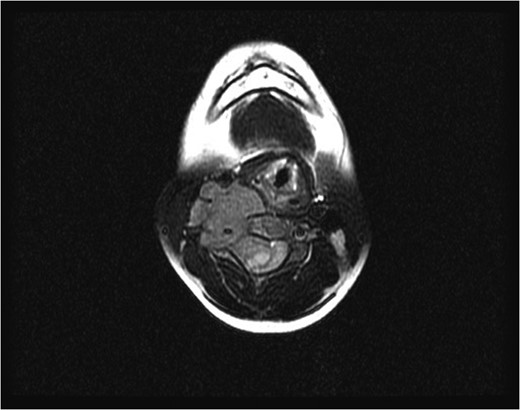

Initial axial magnetic resonance image, showing a tumor compressing the spinal cord and encasing the vertebral artery at the C4 level.